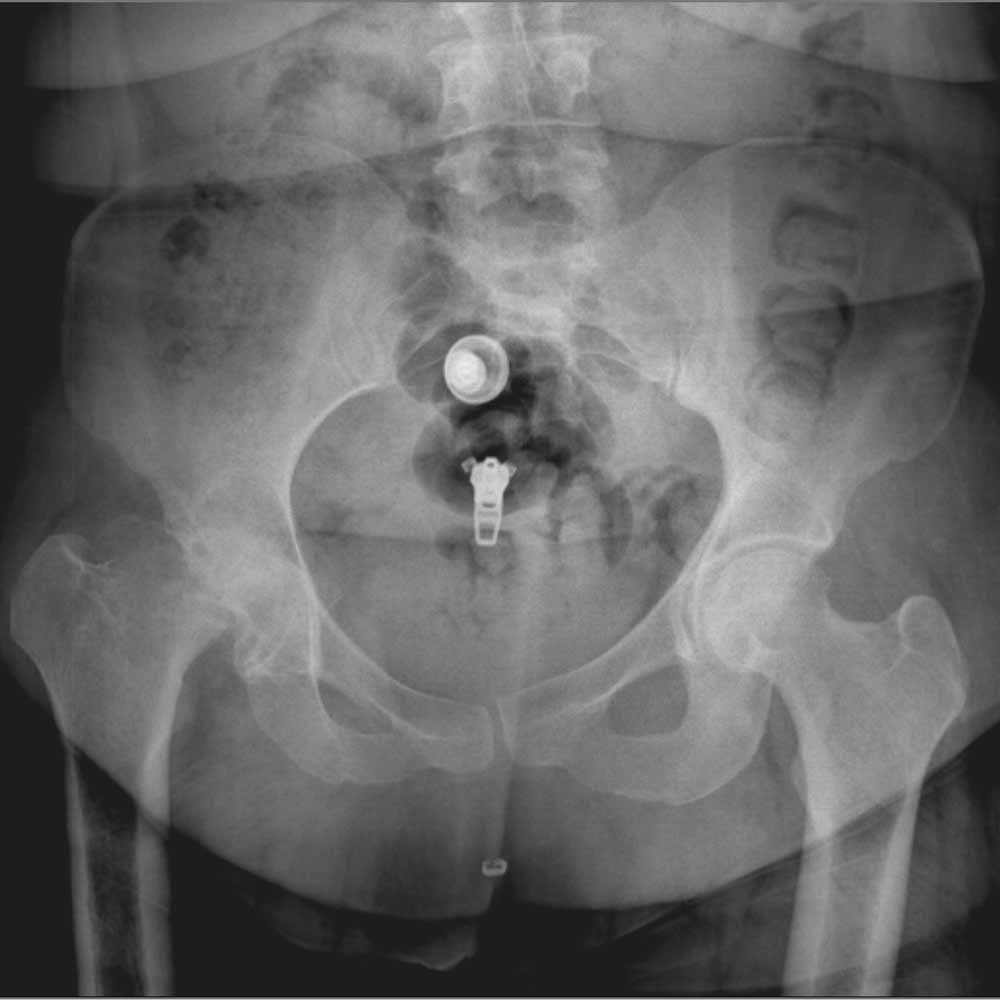

در نهایت، روش های تصویر برداری مثل رادیوگرافی به تشخیص بیماری کمک میکند. مهمترین روش تصویربرداری برای تشخیص ساییدگی لگن رادیوگرافی ساده است. تشخیص این بیماری نیاز به سی تی اسکن یا ام ار آی ندارد.

در تصویر رادیوگرافی از مفصل، چون غضروف نازک شده است فاصله مفصلی یا فاصله بین دو استخوانی که مفصل را تشکیل داده اند و در حد چند میلیمتر است کاهش پیدا میکند و در کناره های استخوان های تشکیل دهنده مفصل استخوان اضافی دیده میشود.

همچنین ممکن است کیست های استخوانی در بالای استابولوم یا در سر استخوان ران دیده شود.

در زیر تصاویری از عکس ساییدگی لگن در چند بیمار را میبینید. با کلیک بر روی هر کدام تصویر بزرگتری از آن را خواهید دید.